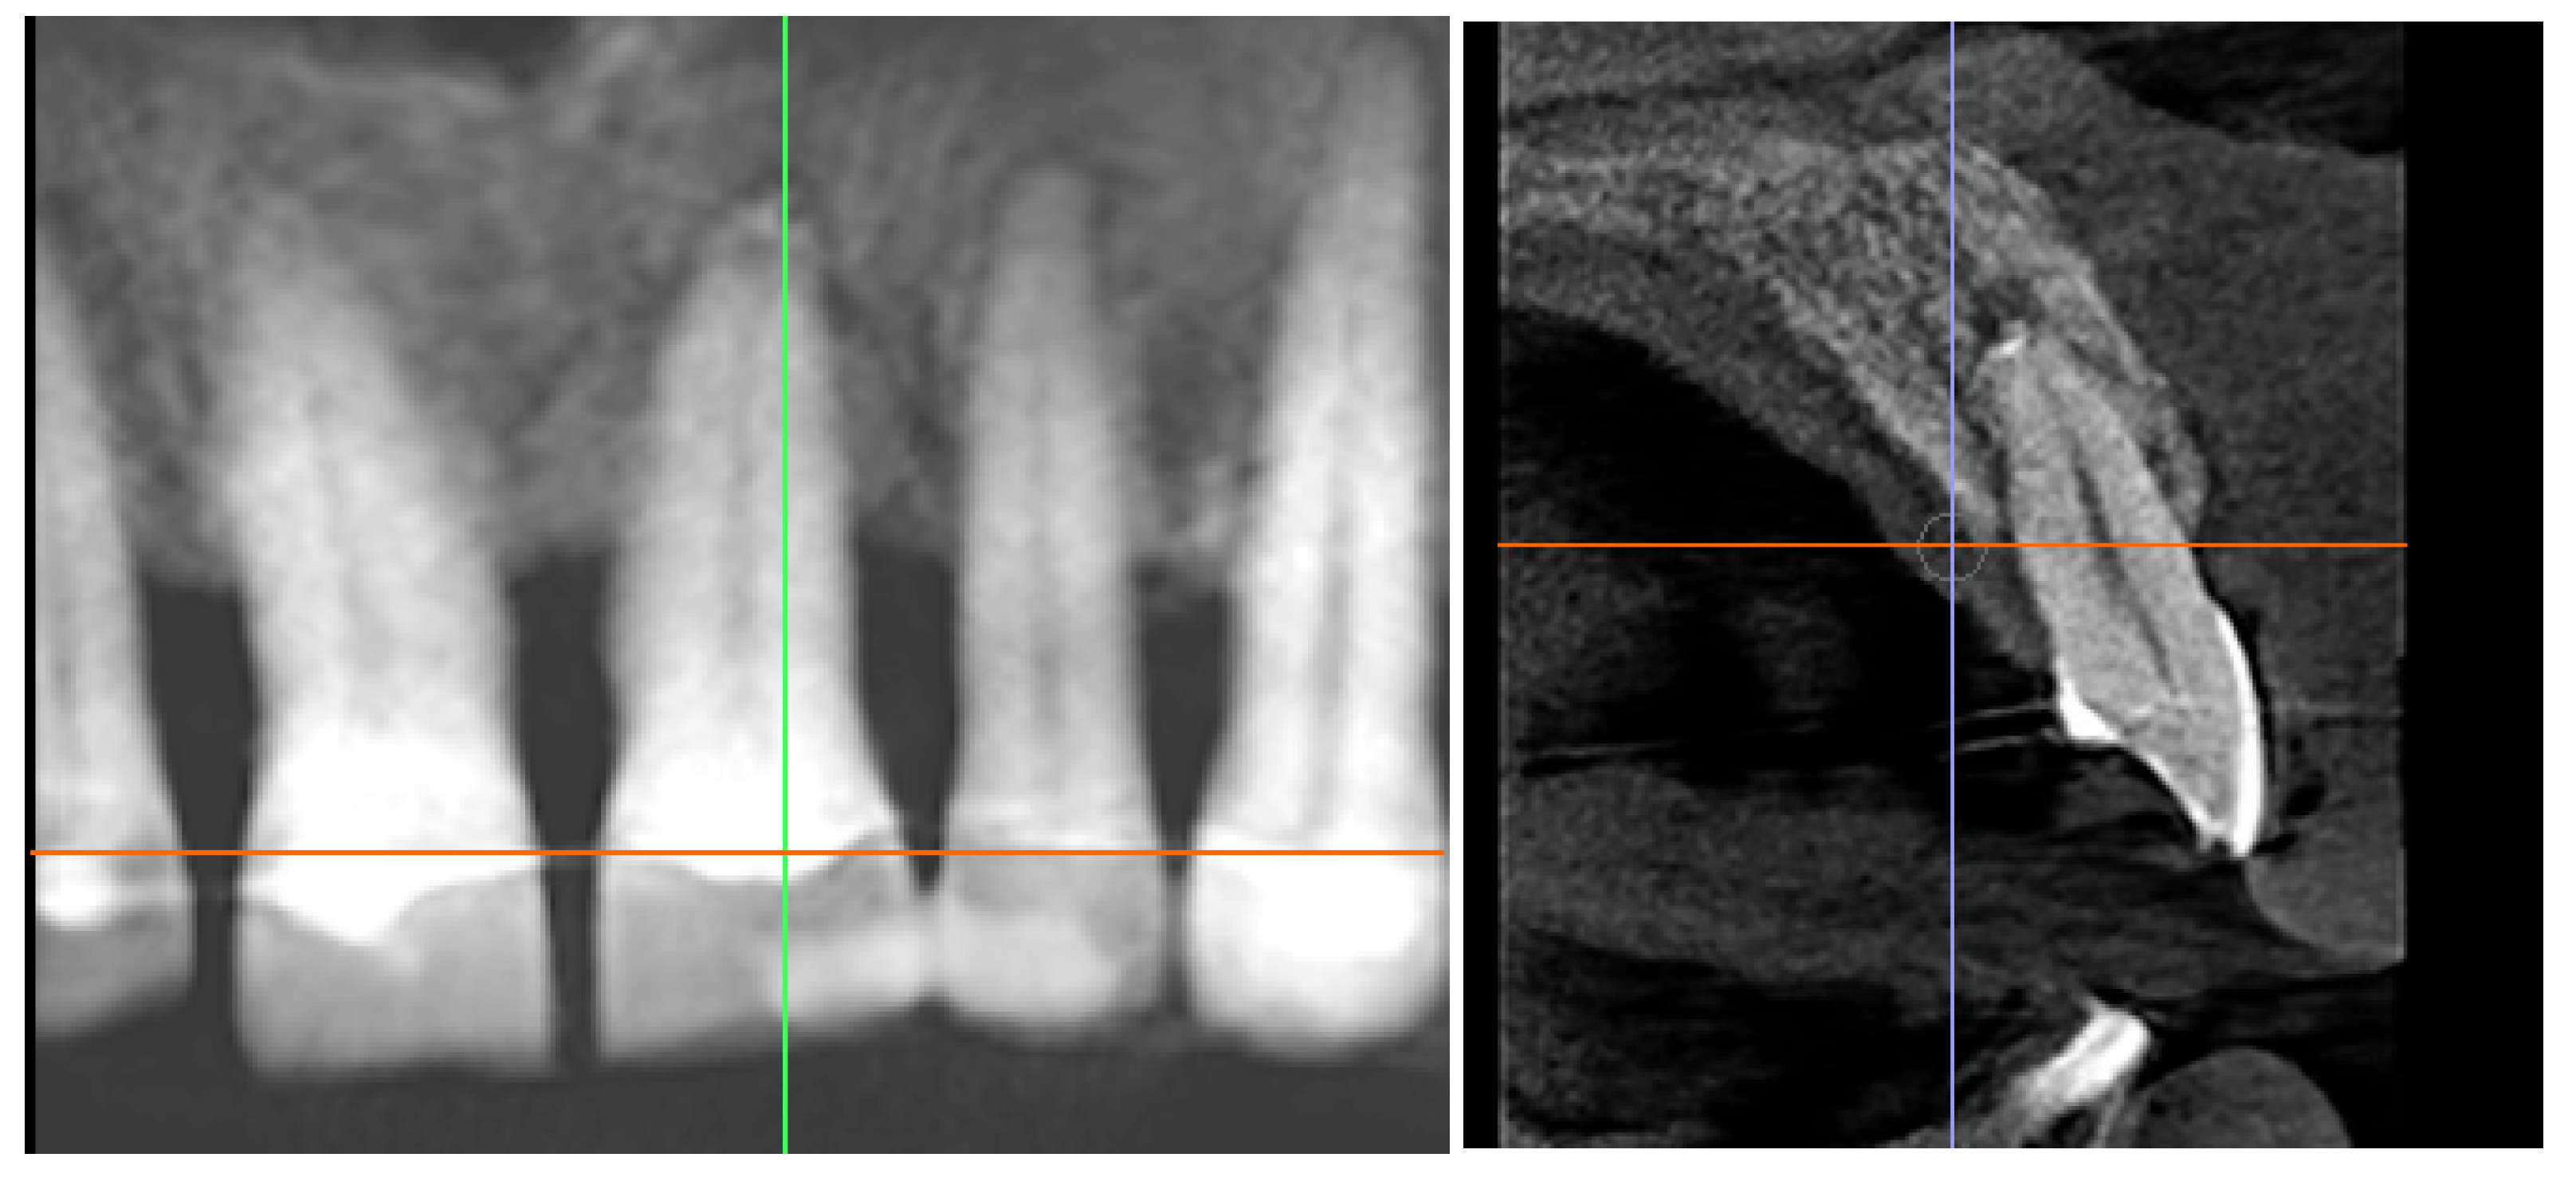

3.2. Radiographic Findings

4.2. Digital Guidance and Socket Preparation

4.3. Regenerative Approach and Endodontic Protocol